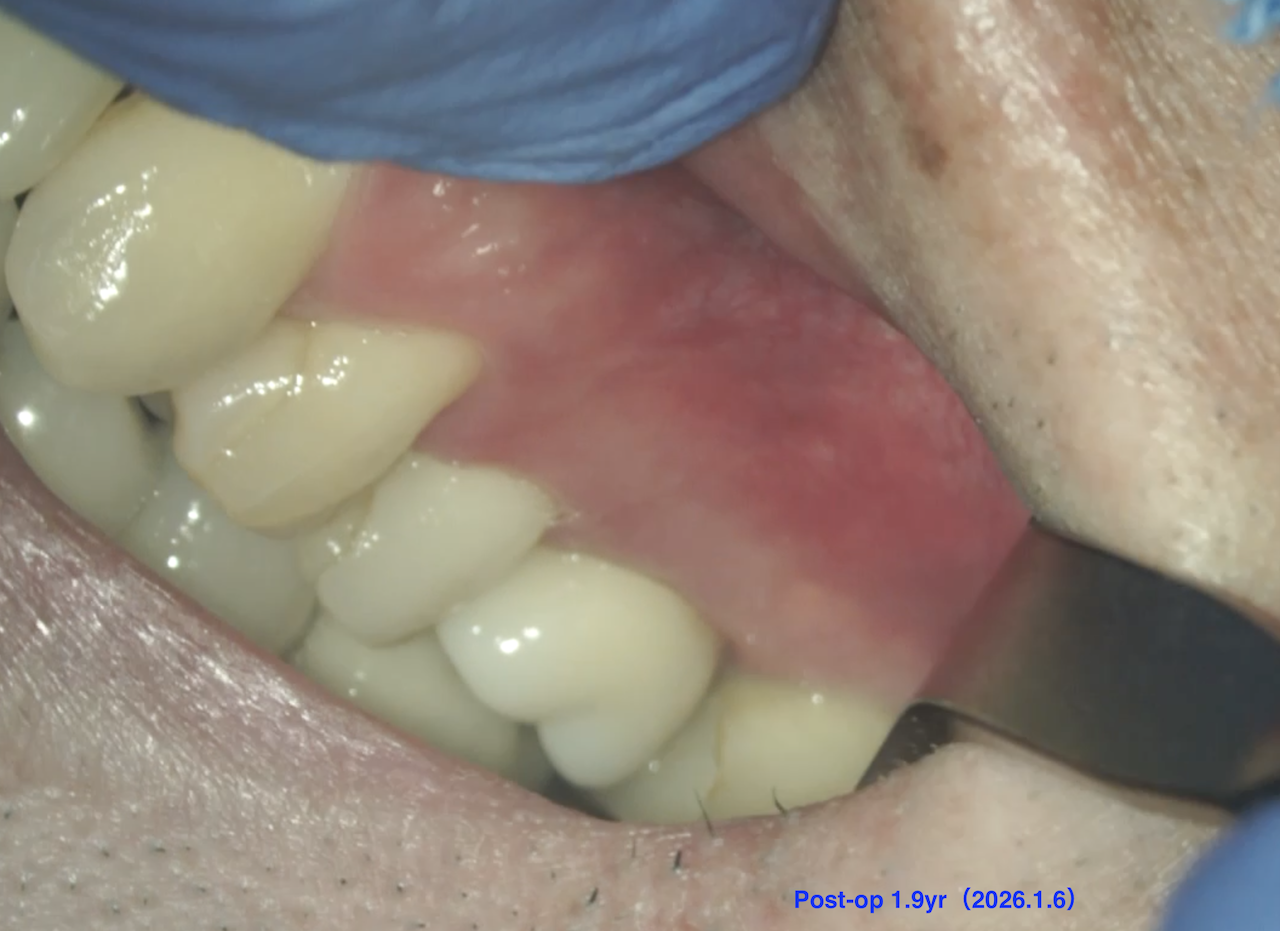

この治療から1.9yr経過していた。

#14 Intentional Replantation 1.9yr recall(2026.1.6)

術前のSinus tractは消失した。

Sinus tractの消失は問題解決の“証拠”である。

初診時と比較した。

問題が劇的に解決していることがわかる。

また、最終補綴も既に装着されていることからこの日で終診とさせていただいた。